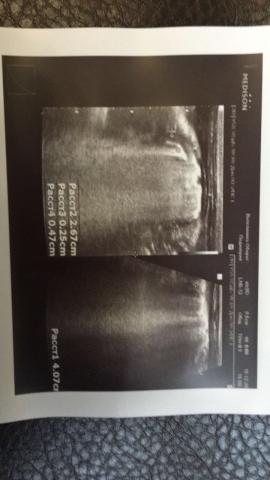

Если можно, то немного подробнее. На основании чего вам поставили такой диагноз, только на основании проведенного УЗИ? Может быть, собаке брали какие-то анализы? Если да, то выложите, пожалуйста, здесь их результаты. Если только данные УЗИ, то это разговор ни о чем (я имею ввиду панкреатит). Гастрит по данным УЗИ вообще не ставят.

К сожалению, ничего не могу рассмотреть. Попробуйте сами прочесть описание с фото. Если сможете, сделайте снимок более качественным. Или можно снять крупнее по частям. Может быть, тогда буквы будут видны более четко.

Спасибо, фотографии четкие. Я все прочитал. Как я и думал, там и "не пахнет" никаким гастродуоденитом, а тем более, панкреатитом.